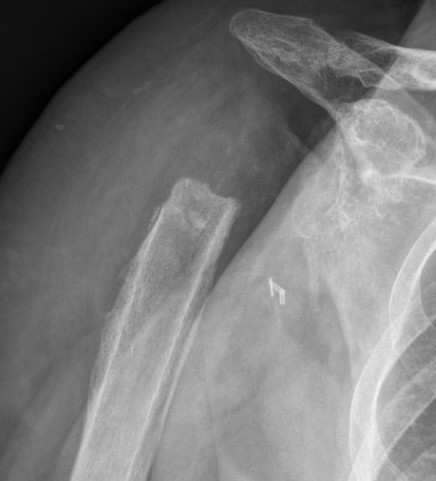

Acromial / scapular spine stress fractures

Incidence

King et al Bone Joint J 2019

- systematic review of rTSA

- incidence 2.8%

- more common with lateralized glenosphere

Usually within first year

Associated with worse clinical outcomes

Cause

- over tensioning deltoid from over lengthening arm / distalizing humerus

- increased risk in women / osteoporosis

- increased risk with superior screw towards scapular spine instead of coracoid

Reverse TSR OvertighteningReverse TSR Overtightening 2

Overlengthened arm post rTSA

Acromial stress fracture

Acromial stress fracture on xray